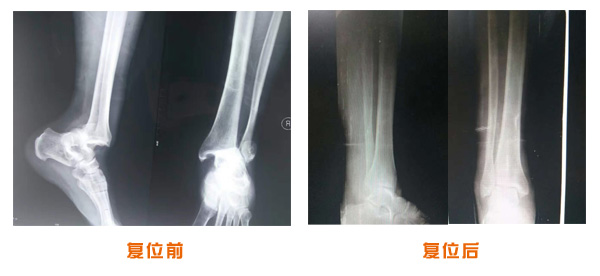

復位前后對比